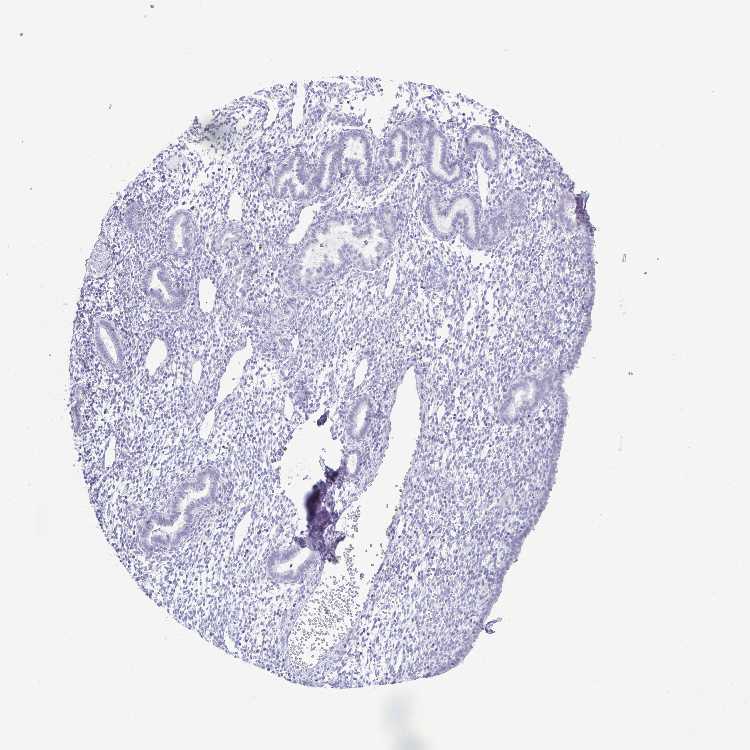

ENDOMETRIUM 1 - Antibody stainingi

Antibody staining in the annotated cell types in the current human tissue is reported as not detected, low, medium, or high, based on conventional immunohistochemistry profiling in selected tissues. This score is based on the combination of the staining intensity and fraction of stained cells.

Each image is clickable and will lead to virtual microscopy that enables deeper exploration of all samples and also displays staining intensity scores, fraction scores and subcellular localization as well as patient and tissue information for each sample.

ENDOMETRIUM 2 - Antibody stainingi